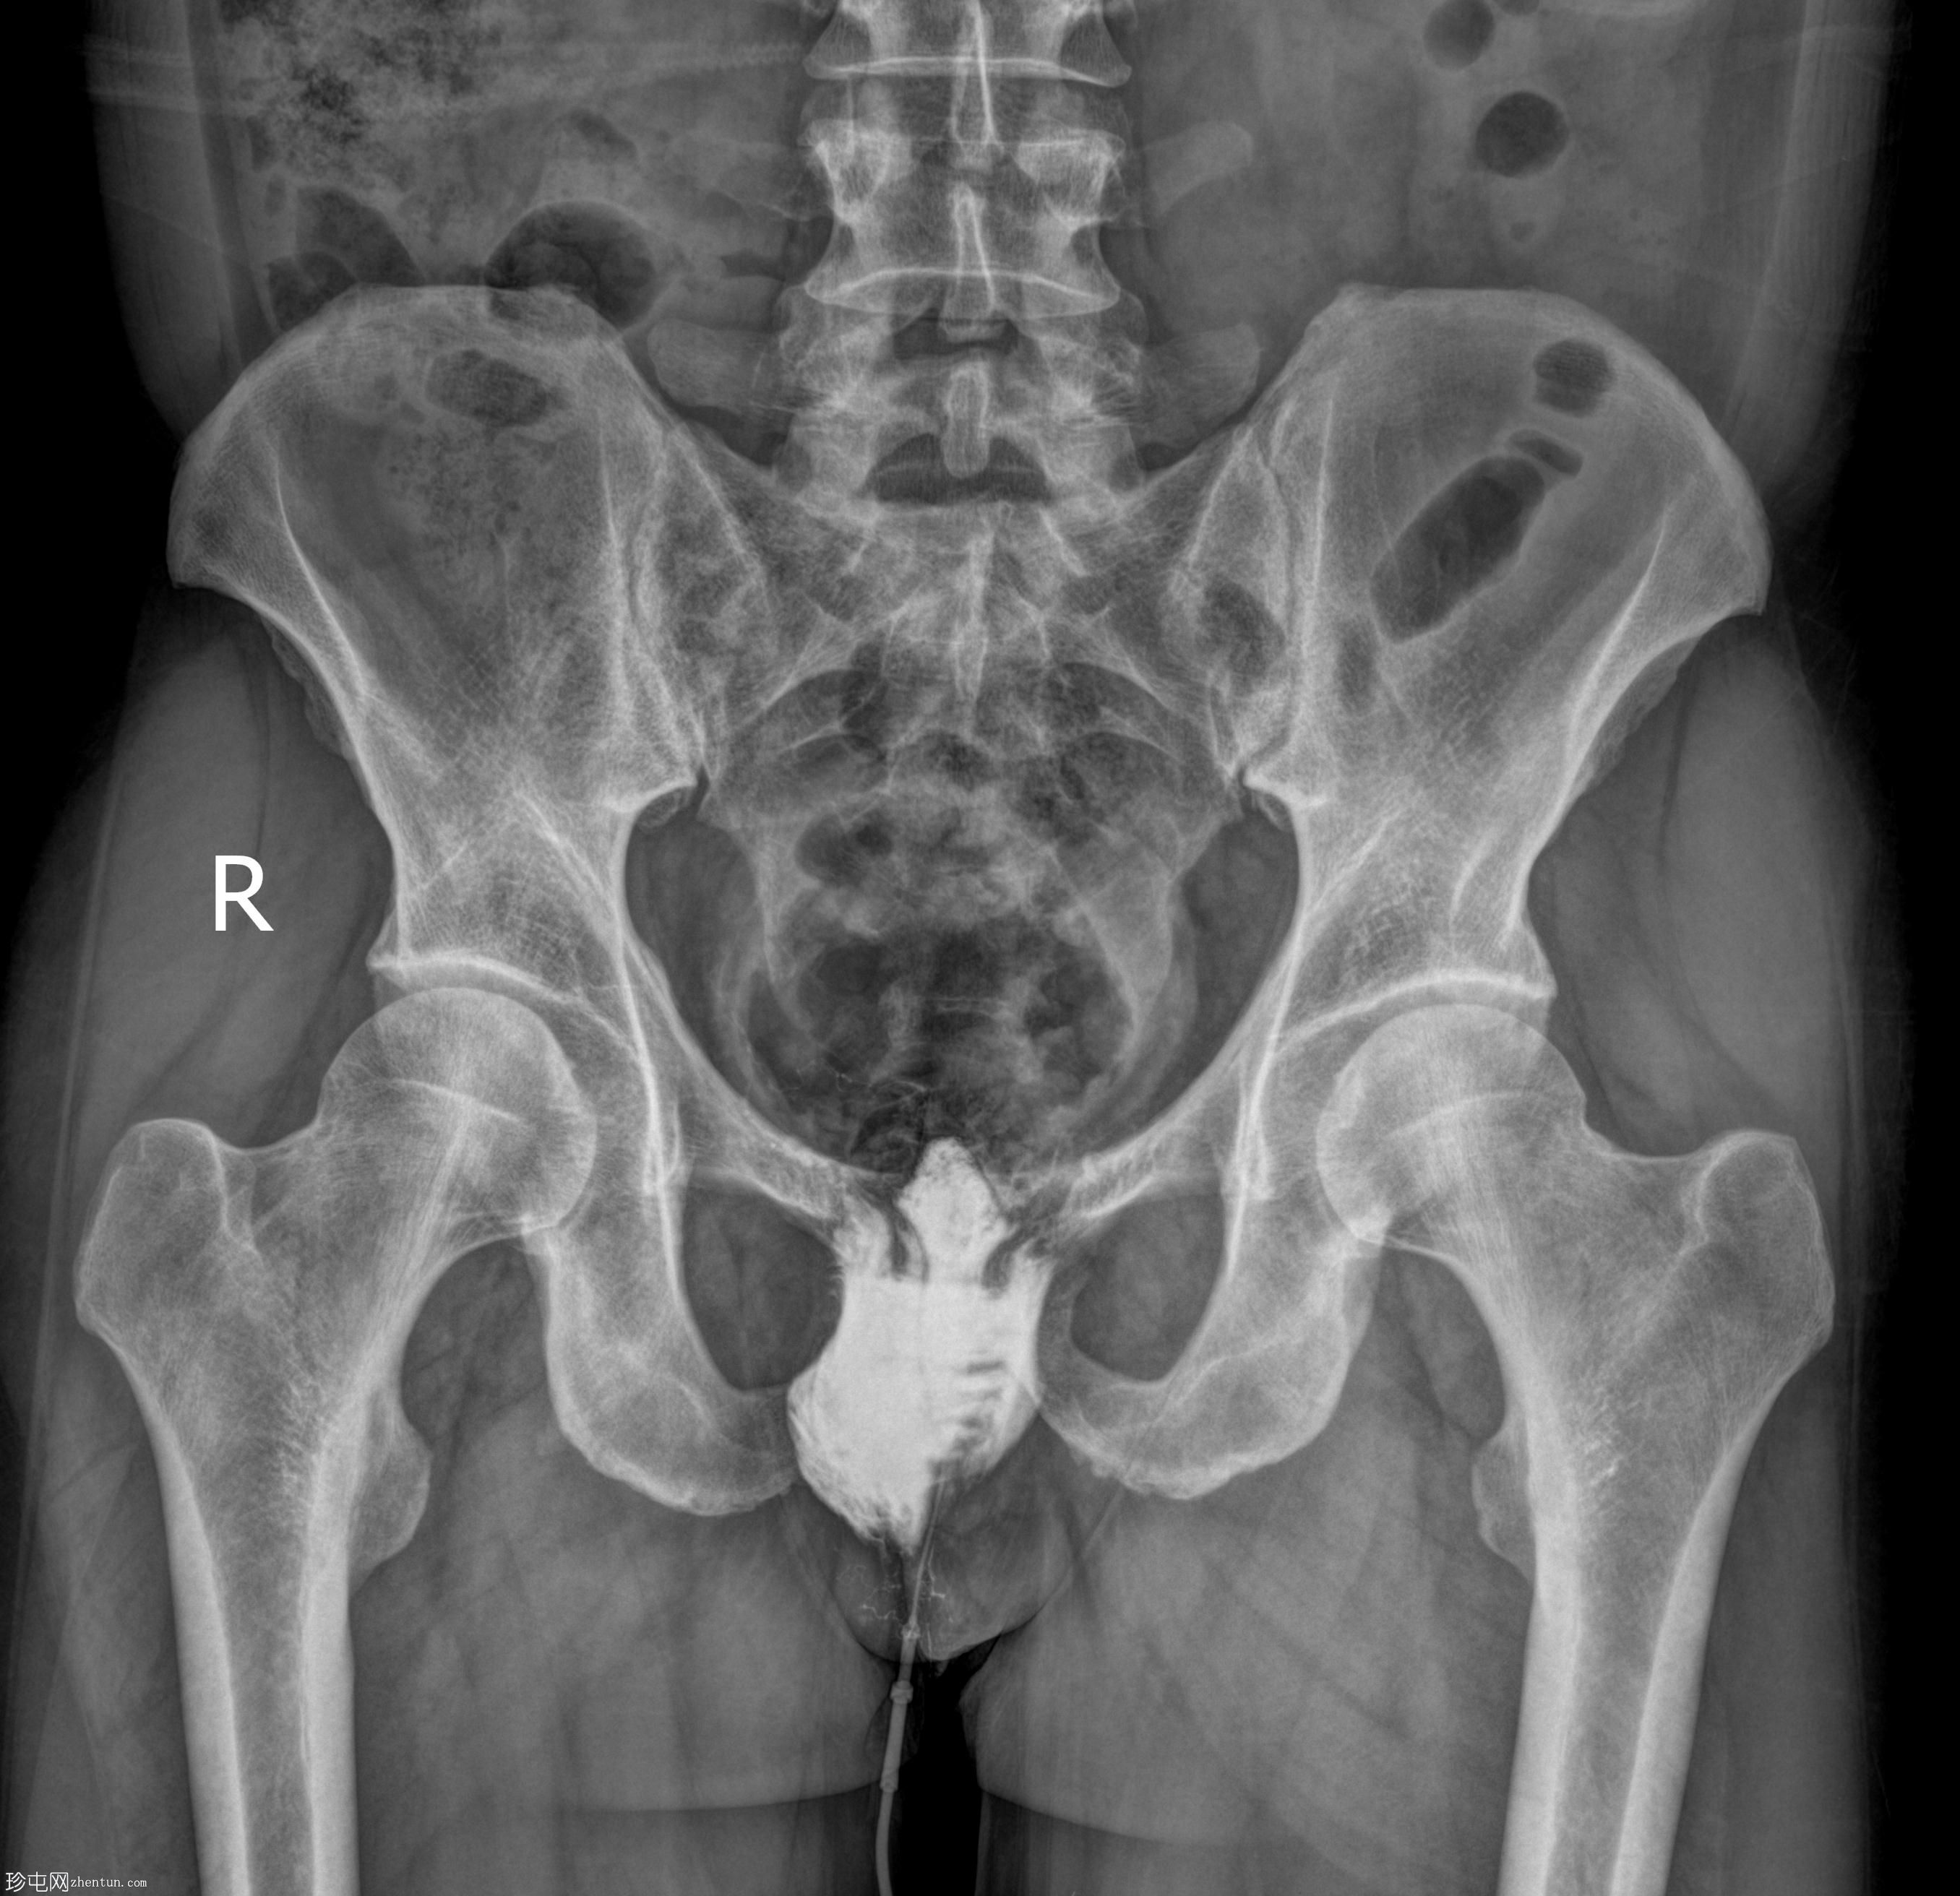

年龄:50岁

性别:男

透视检查

经脓性分泌物开口注入造影剂,显示右侧肛周脓肿显影。

未见造影剂明显外渗至肛管或直肠。

透视瘘管造影图像显示右侧肛周脓肿较大,与肛管或直肠无交通。